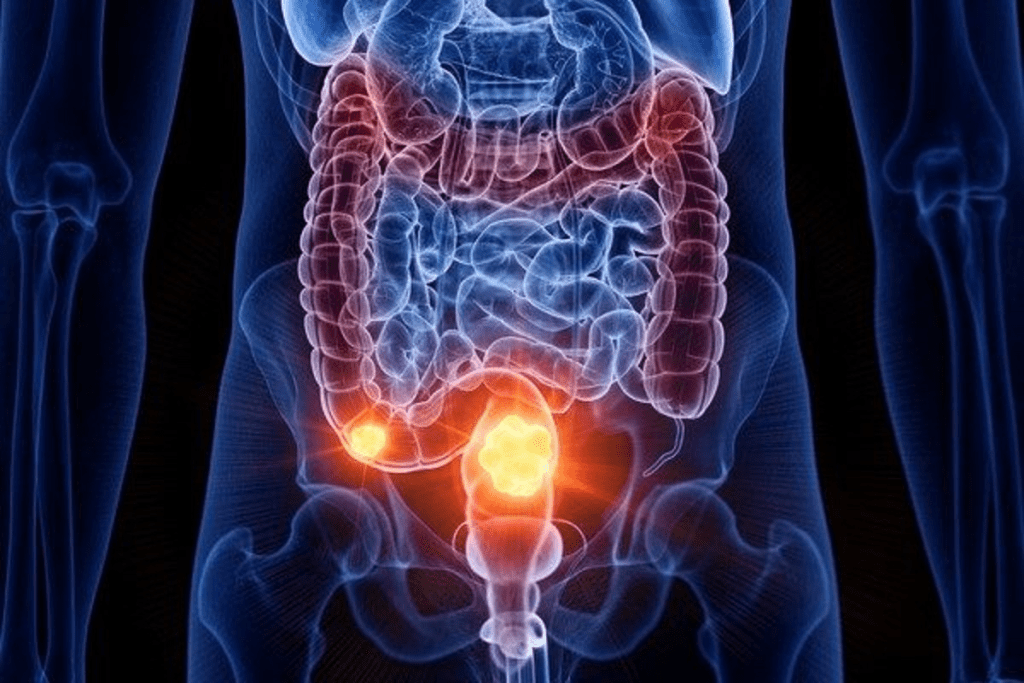

Location-Specific Colon Cancers and Their Progression

Knowing how colon cancer spreads based on its location is key for treatment. The colon’s shape and size affect cancer’s growth and spread. Cancers in different parts of the colon behave differently.

Cecum Cancer and Its Spread Patterns

Cecum cancer, found at the start of the large intestine, poses unique challenges. The cecum is a pouch where the small intestine meets the large intestine. Cancers here can grow big before symptoms appear, leading to a late diagnosis. Cecum cancer can spread aggressively, affecting nearby areas or distant parts of the body.

Sigmoid Tumors and Their Progression

Sigmoid colon tumors, located in the lower colon, behave differently than cecum cancers. These tumors can block the colon because of their narrow location. Sigmoid tumors can grow fast if not caught early, spreading to lymph nodes and other organs.

How Location Affects Detection and Spread

The colon cancer greatly influences its detection and spread. Cancers in easier-to-reach areas, like the sigmoid colon, are often found sooner. In contrast, cancers in harder-to-reach spots, like the cecum, might be diagnosed later. The cancer’s closeness to lymph nodes and blood vessels also affects its spread rate and pattern.

The National Cancer Institute says the colon cancer impacts its growth and detection. It’s important for doctors to understand these differences to plan treatments. It also helps patients know what to expect based on their cancer’s location.

Metastasis: How and Where Colon Cancer Spreads

Metastasis in colon cancer happens when cancer cells leave the main tumor and go to other body parts. This is a big worry for both patients and doctors. It makes treatment harder and changes how well the patient will do.

Common Sites of Metastasis

Colon cancer often goes to certain organs because of blood flow and the organ’s environment. The most common places include:

- The liver, because of its blood supply and direct connection from the colon.

- The lungs, as cancer cells can travel through the blood to get there.

- The peritoneum, the lining of the belly, can also get cancer cells from the colon.

The American Cancer Society says colon cancer often goes to the liver, lungs, and other organs. Knowing these common places is key for watching and managing the disease.